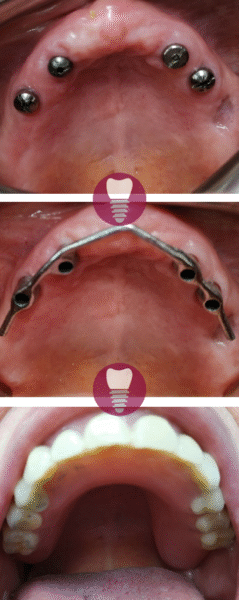

Este caso clínico muestra un tratamiento de restauración completa de la dentadura superior. Este tipo de intervención es ideal para pacientes que presentan una pérdida significativa de piezas dentales en la arcada superior o que tienen dientes gravemente dañados debido a caries avanzadas, desgaste, o problemas periodontales.

En este tratamiento, se emplea una prótesis sobre barra en implantes, proporcionando una solución estable y estética que permite recuperar la funcionalidad y la apariencia de la sonrisa. Este enfoque no solo mejora la capacidad de masticación del paciente, sino que también refuerza la estructura facial y restaura la confianza en su aspecto.

Gracias a la planificación digital y los materiales de alta calidad utilizados, el resultado es duradero y natural.